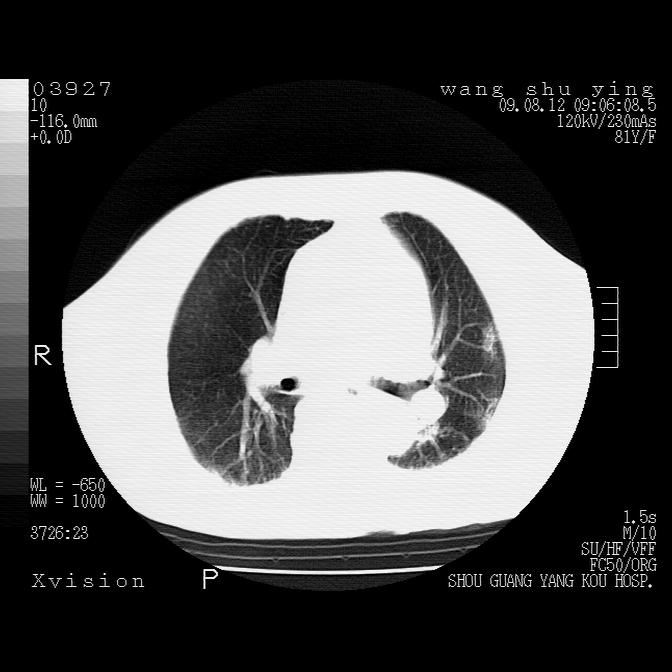

以下是引用帅河马在2009-8-12 12:59:00的发言:[br]两肺感染性病变伴双侧胸膜肥厚。[br]左侧甲状腺腺瘤不除外。[br]腹水+心包积液。[br][br][本贴已被 帅河马 于 2009-8-12 13:14:32 修改过]

以下是引用sdzyy在2009-8-12 18:17:00的发言:[br]两肺感染性病变伴双侧胸膜肥厚。[br]左侧甲状腺腺瘤不除外。[br]腹水+心包积液。[br]支持

以下是引用随光逐影在2009-8-12 19:42:00的发言:[br]1)两肺感染性病变伴双侧胸膜肥厚。2)不排除左侧甲状腺腺瘤。3)肝脏占位性病变;建议行进一步检查。